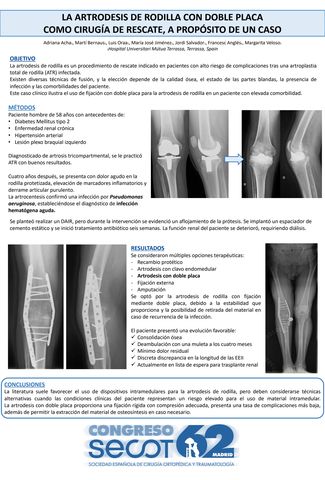

La artrodesis de rodilla con doble placa como cirugía de rescate, a propósito de un caso

ADRIANA ACHA SUÑER, LUIS ORAA LOPEZ, MARTÍ CARLES BERNAUS JOHNSON, MARGARITA VELOSO DURAN, FRANCISCO ANGLES CRESPO